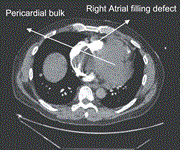

Primary pericardial synovial sarcoma requiring emergency salvage right atrial debulking: a case report

Ramanish Ravishankar and others

Journal of Surgical Case Reports, Volume 2024, Issue 6, June 2024, rjae372, https://doi.org/10.1093/jscr/rjae372